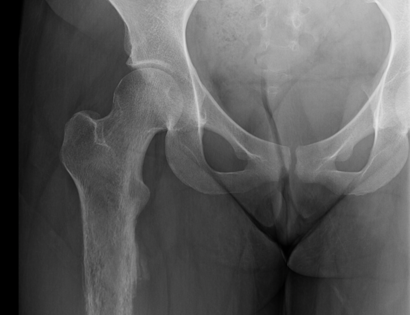

This is an x-ray of the femur prior to surgery. The tumor is located on in the entirety of the femur bone seen in the photo.